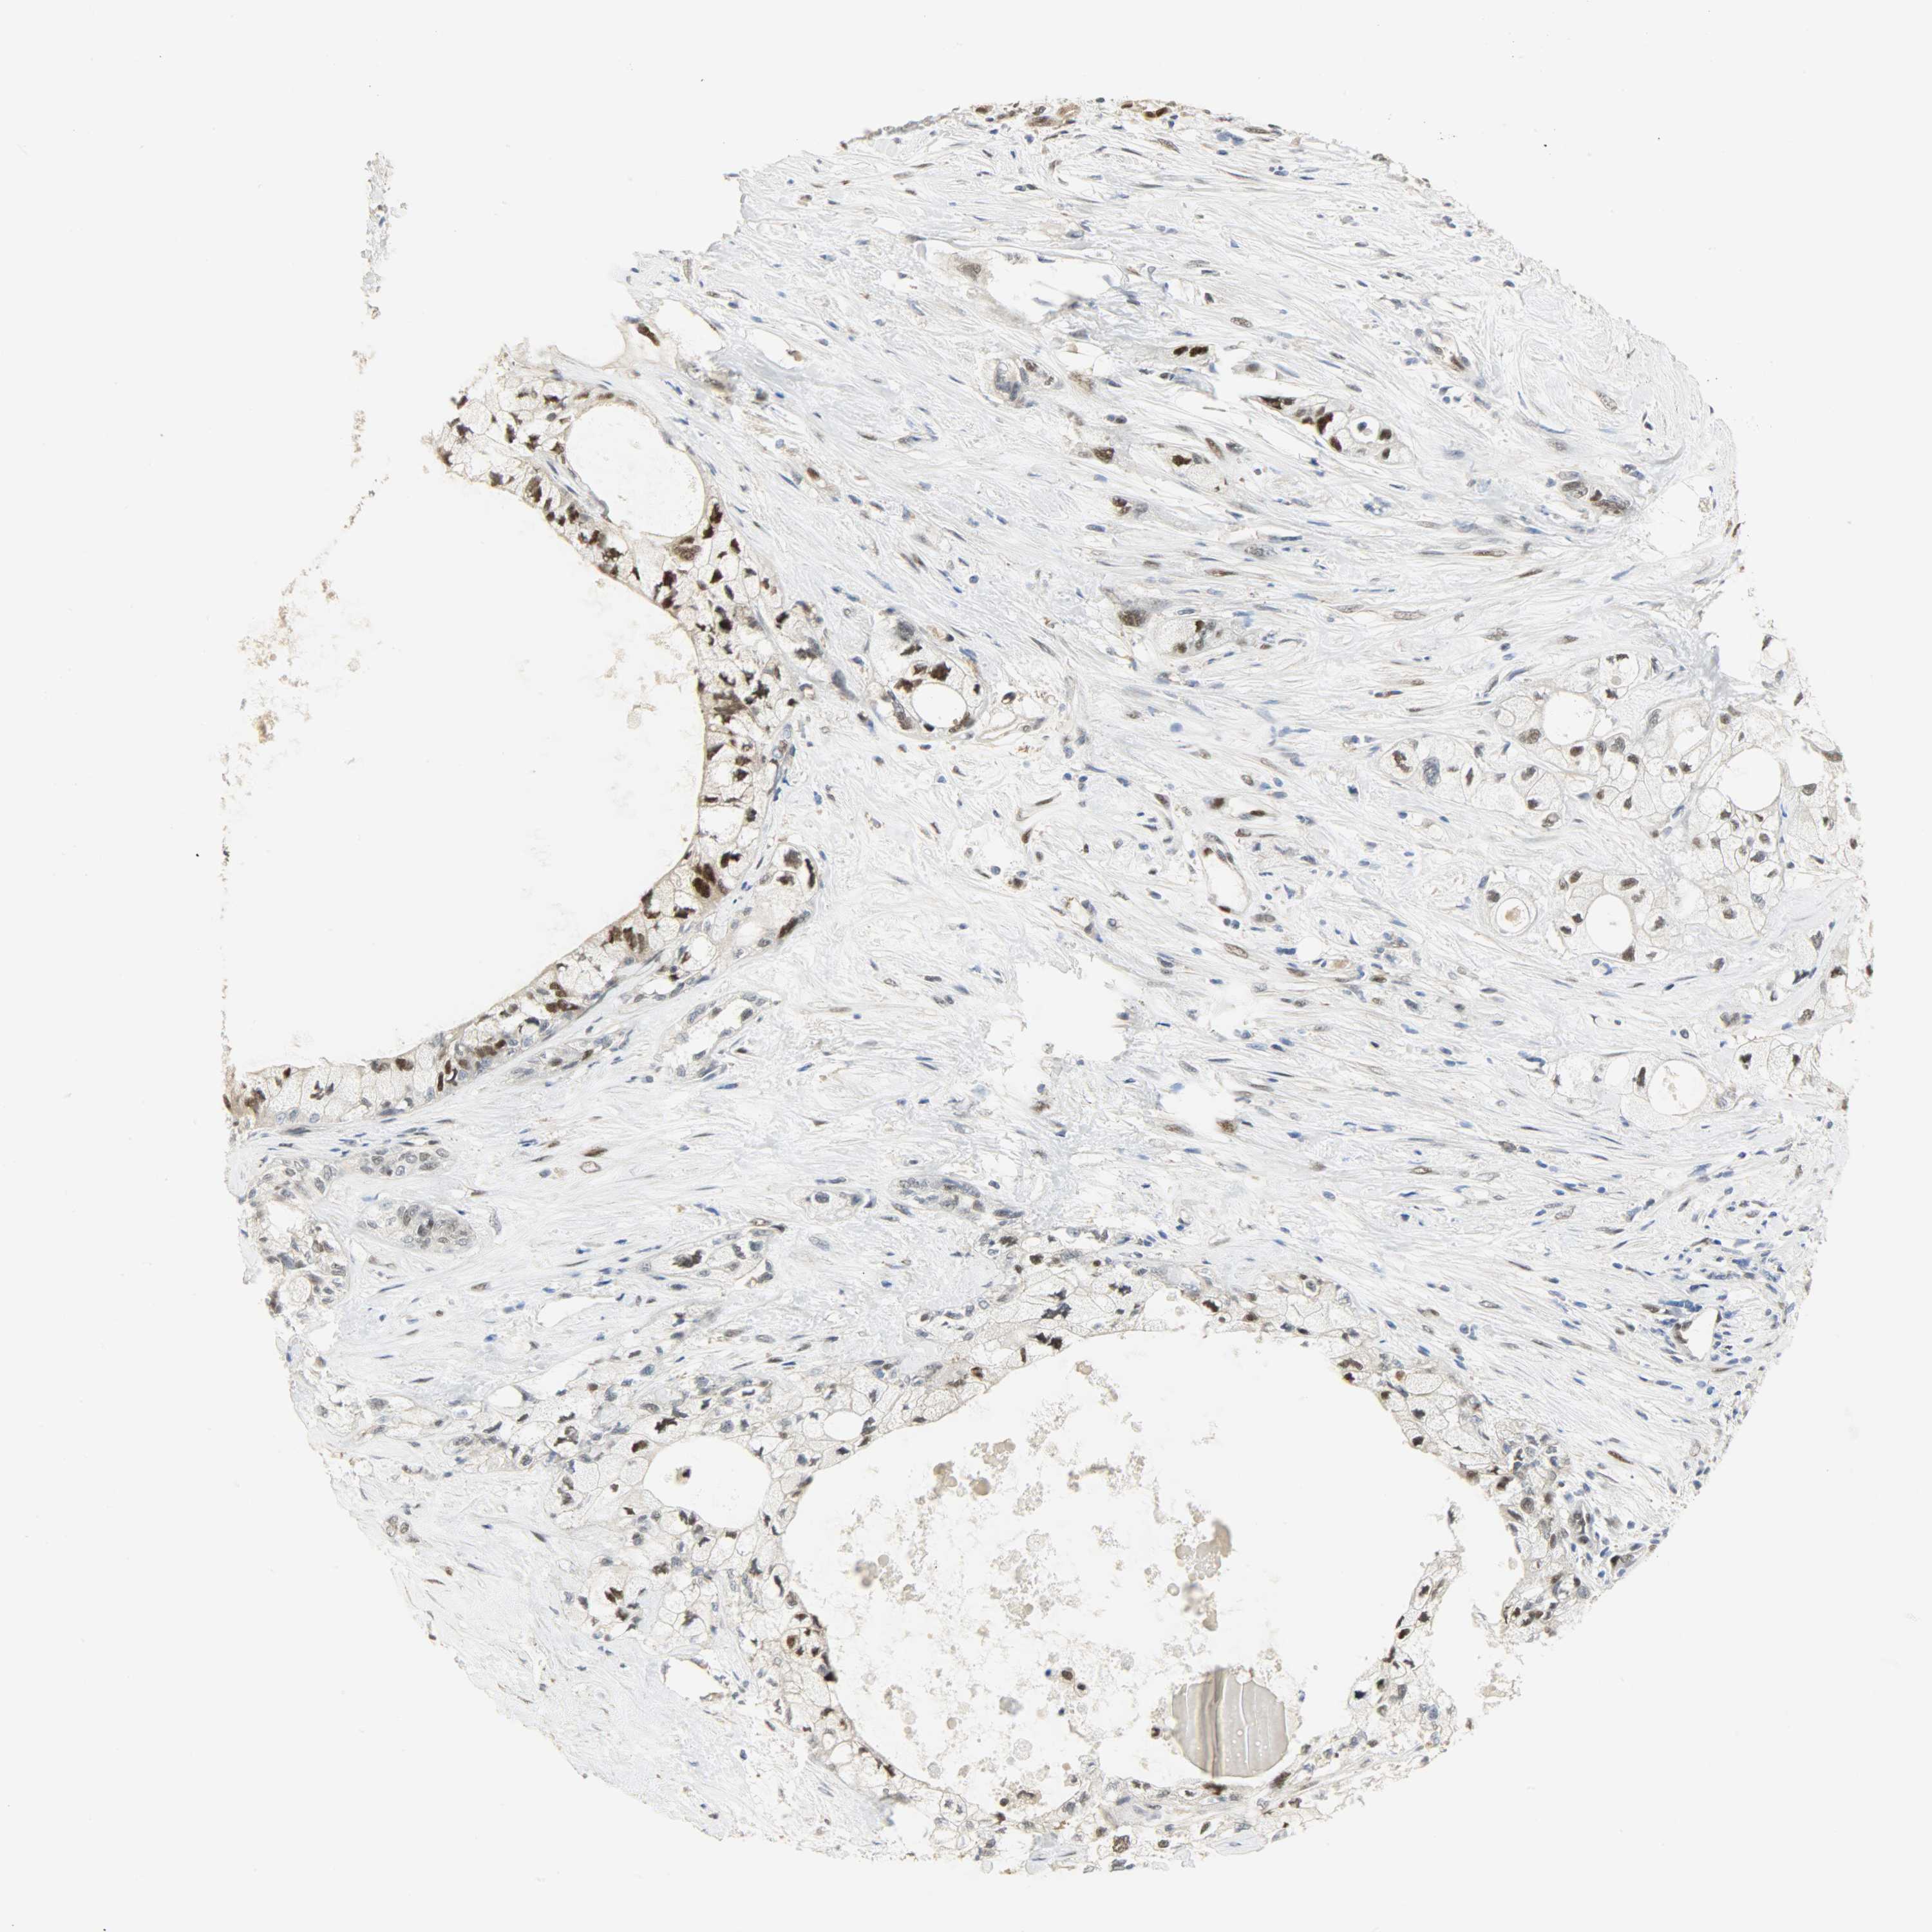

PANCREATIC CANCER - Protein expressioni

A mouse-over function shows sample information and annotation data. Click on an image to view it in a full screen mode. Samples can be filtered based on level of antibody staining by selecting one or several of the following categories: high, medium, low and not detected. The assay and annotation is described here.

Note that samples used for immunohistochemistry by the Human Protein Atlas do not correspond to samples in the TCGA dataset.

Antibody stainingi

Antibody staining in the annotated cell types in the current human tissue is reported as not detected, low, medium, or high, based on conventional immunohistochemistry profiling in selected tissues. This score is based on the combination of the staining intensity and fraction of stained cells.

Each image is clickable and will lead to virtual microscopy that enables deeper exploration of all samples and also displays staining intensity scores, fraction scores and subcellular localization as well as patient and tissue information for each sample.

Antibody HPA036356

Antibody CAB004986

Antibody CAB017025

Staining

High

Medium

Low

Not detected

Intensity

Strong

Moderate

Weak

Negative

Quantity

>75%

75%-25%

<25%

None

Location

Nuclear

Cytoplasmic/membranous

Cytoplasmic/membranous,nuclear

Adenocarcinoma, NOS

Adenocarcinoma, metastatic, NOS